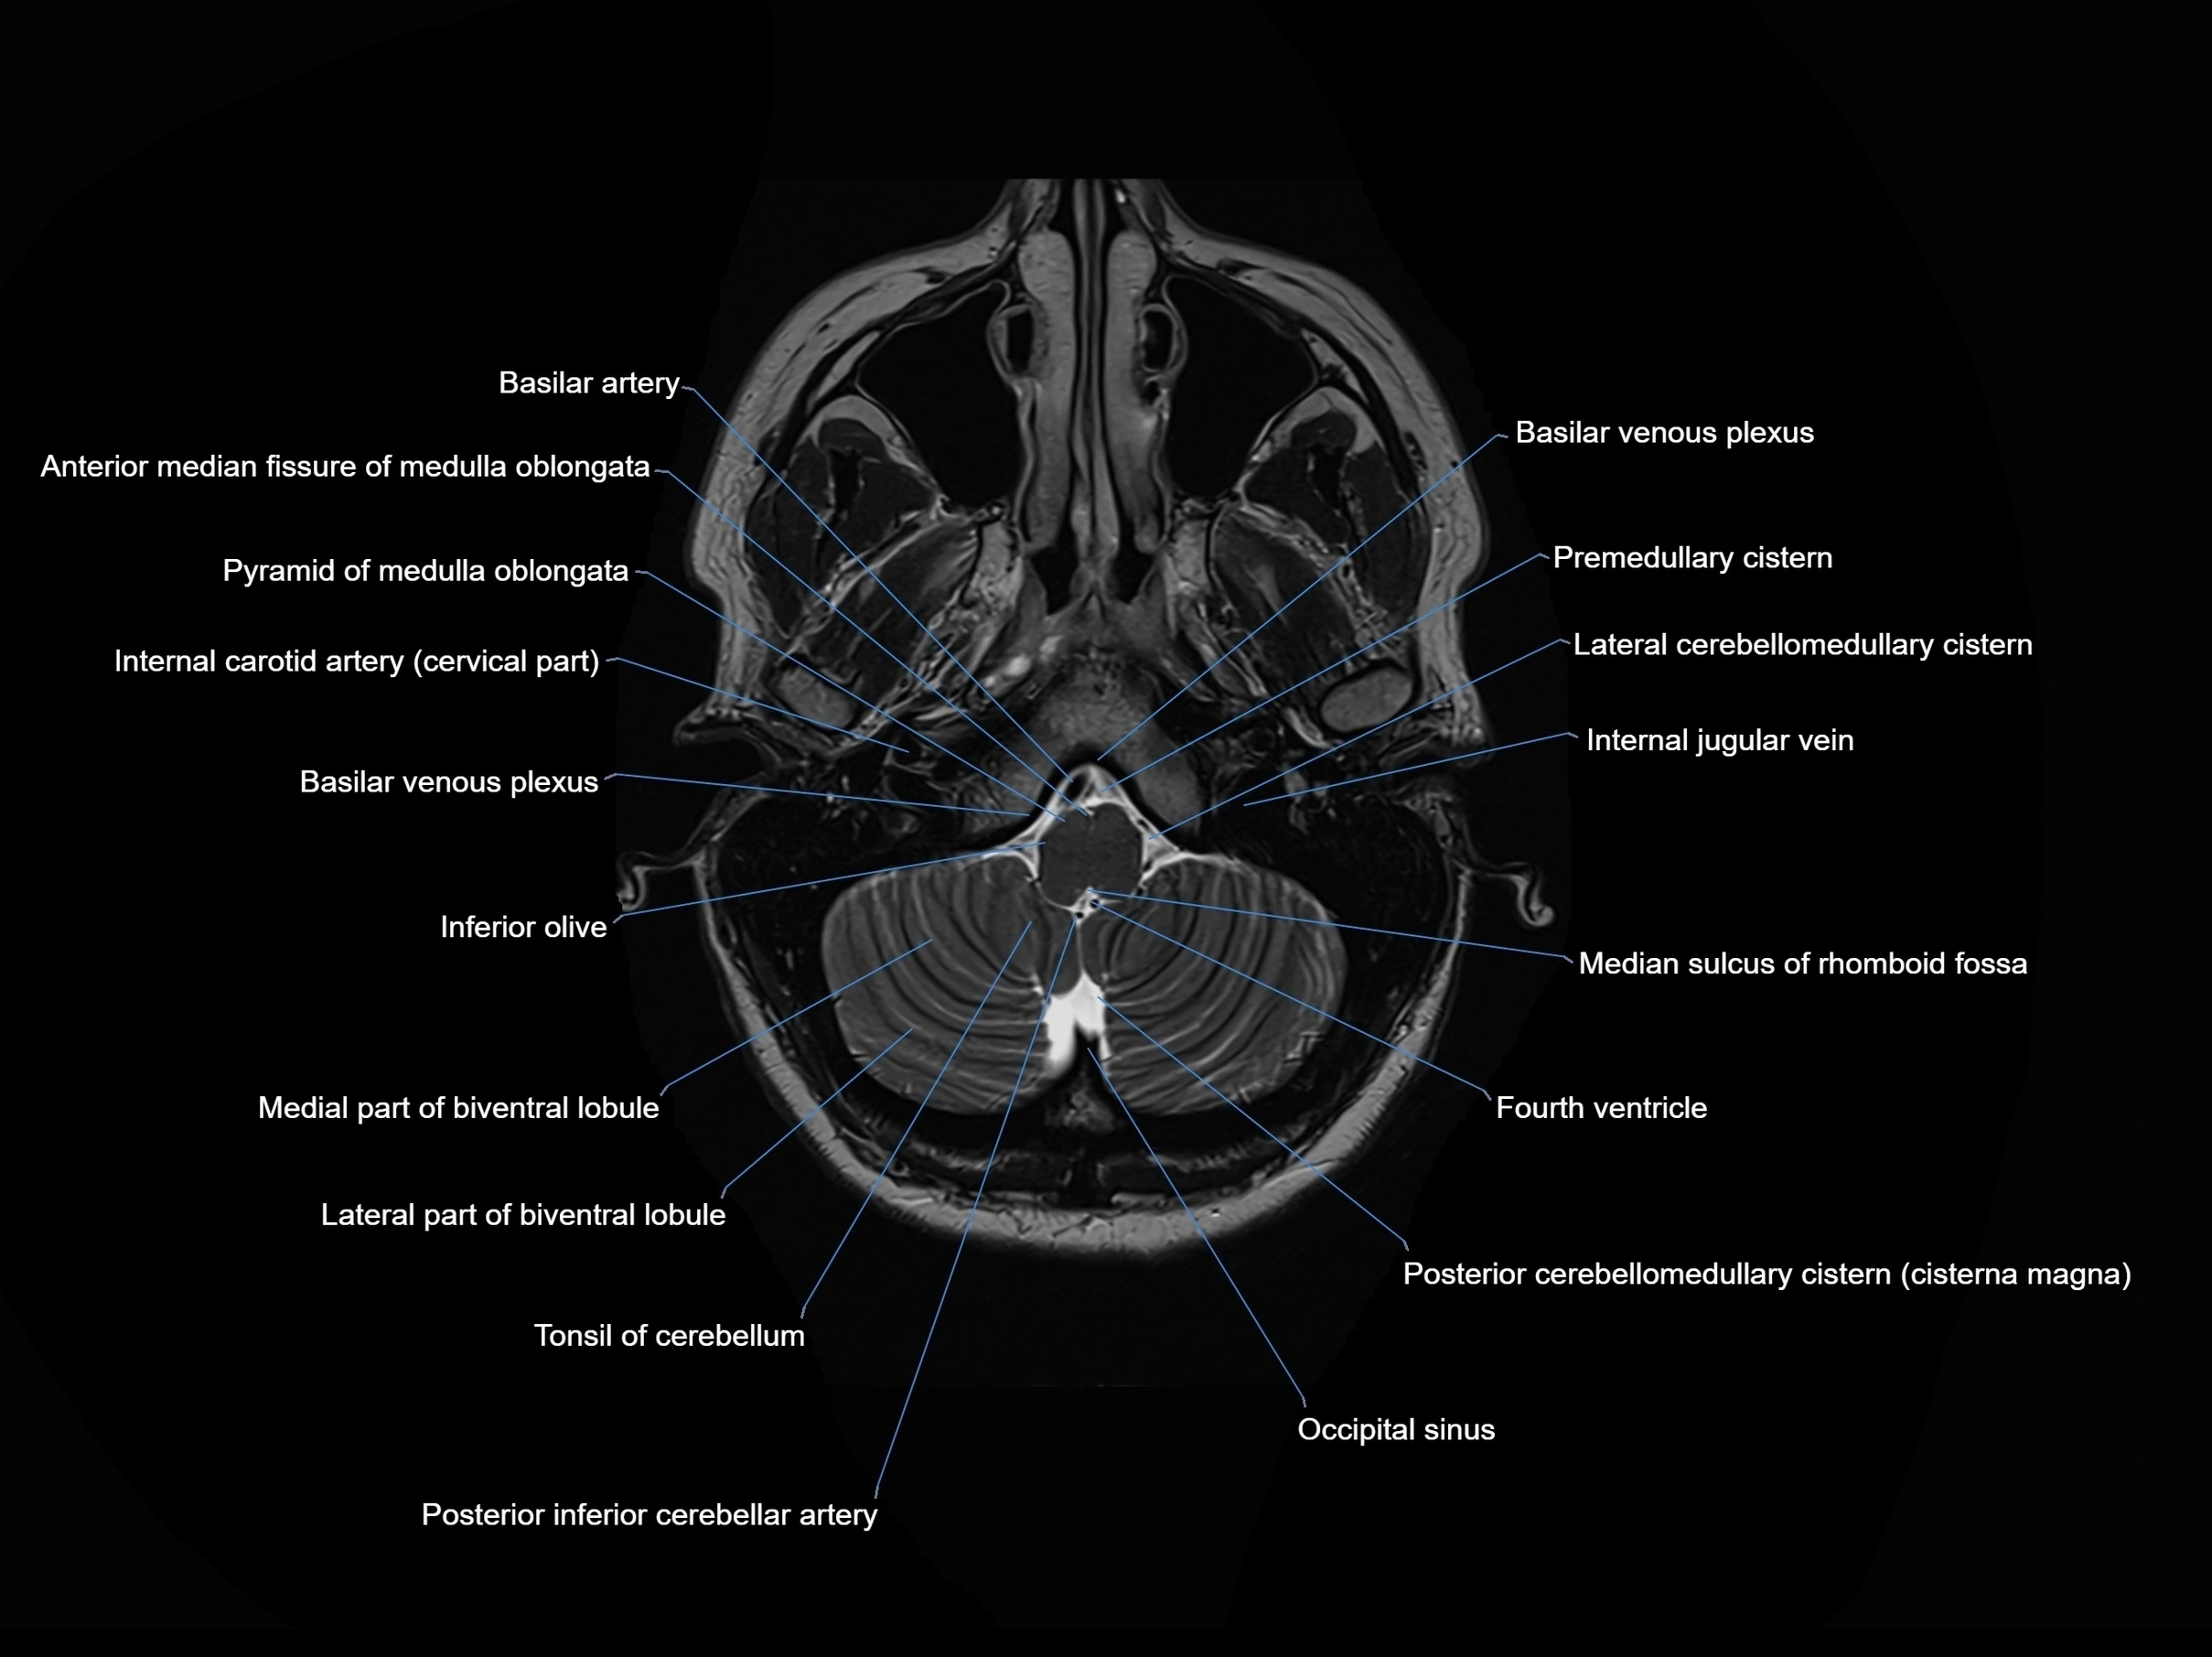

- Anterior median fissure of medulla oblongata

- Basilar artery

- Basilar venous plexus

- Fourth ventricle

- Inferior olive

- Lateral cerebellomedullary cistern

- Internal jugular vein

- Median sulcus of rhomboid fossa

- Posterior cerebellomedullary cistern (cisterna magna)

- Posterior inferior cerebellar artery

- Premedullary cistern

- Pyramid of medulla oblongata